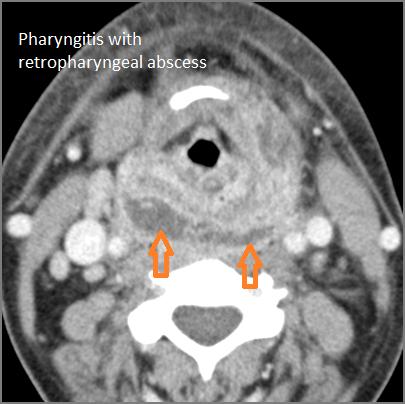

There is edema within the adjacent deep neck, retropharyngeal and/or prevertebral spaces.

There is abscess within the adjacent deep neck, retropharyngeal and/or prevertebral spaces.